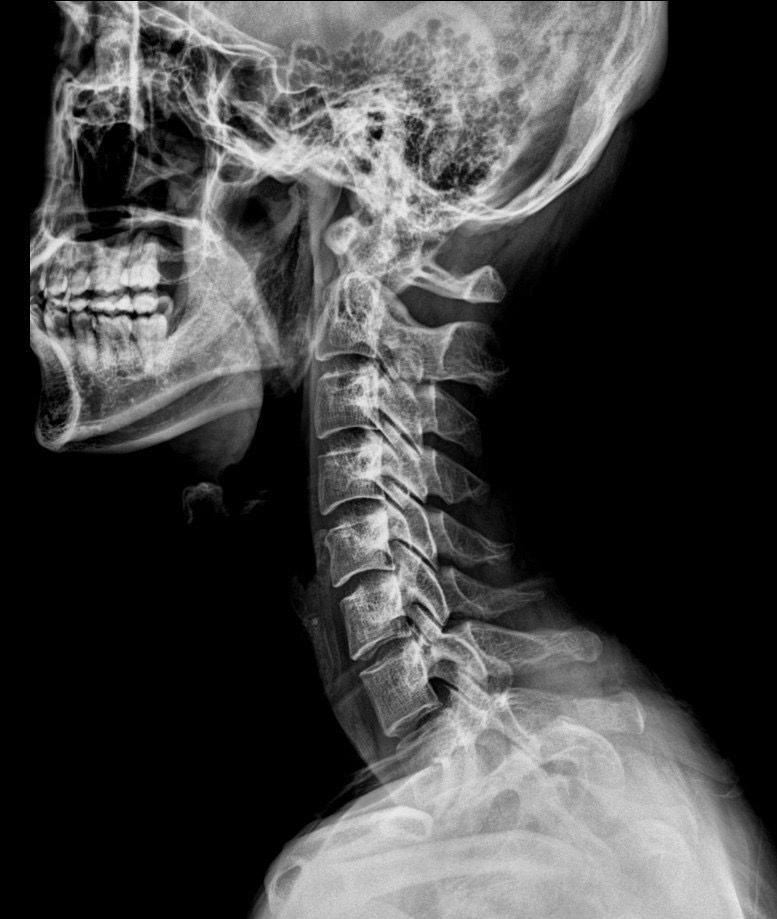

병원에서 일자목이면 경추성 어지럼증도 의심을 해보라고 하더라구요. 그래서 정형외과를 가서 엑스레이를 일단 찍어봤는데 전체적인 척추정렬이 삐둘어져있고 상부경추가 일자목이라서 의심은 된다고 하나 확답은 못주시네요.

여러 전문가분들께서 사진을 보시고 그 확률이 얼마나 될지 많은 조언을 주시면 감사하겠습니다.

• 2번 째 사진